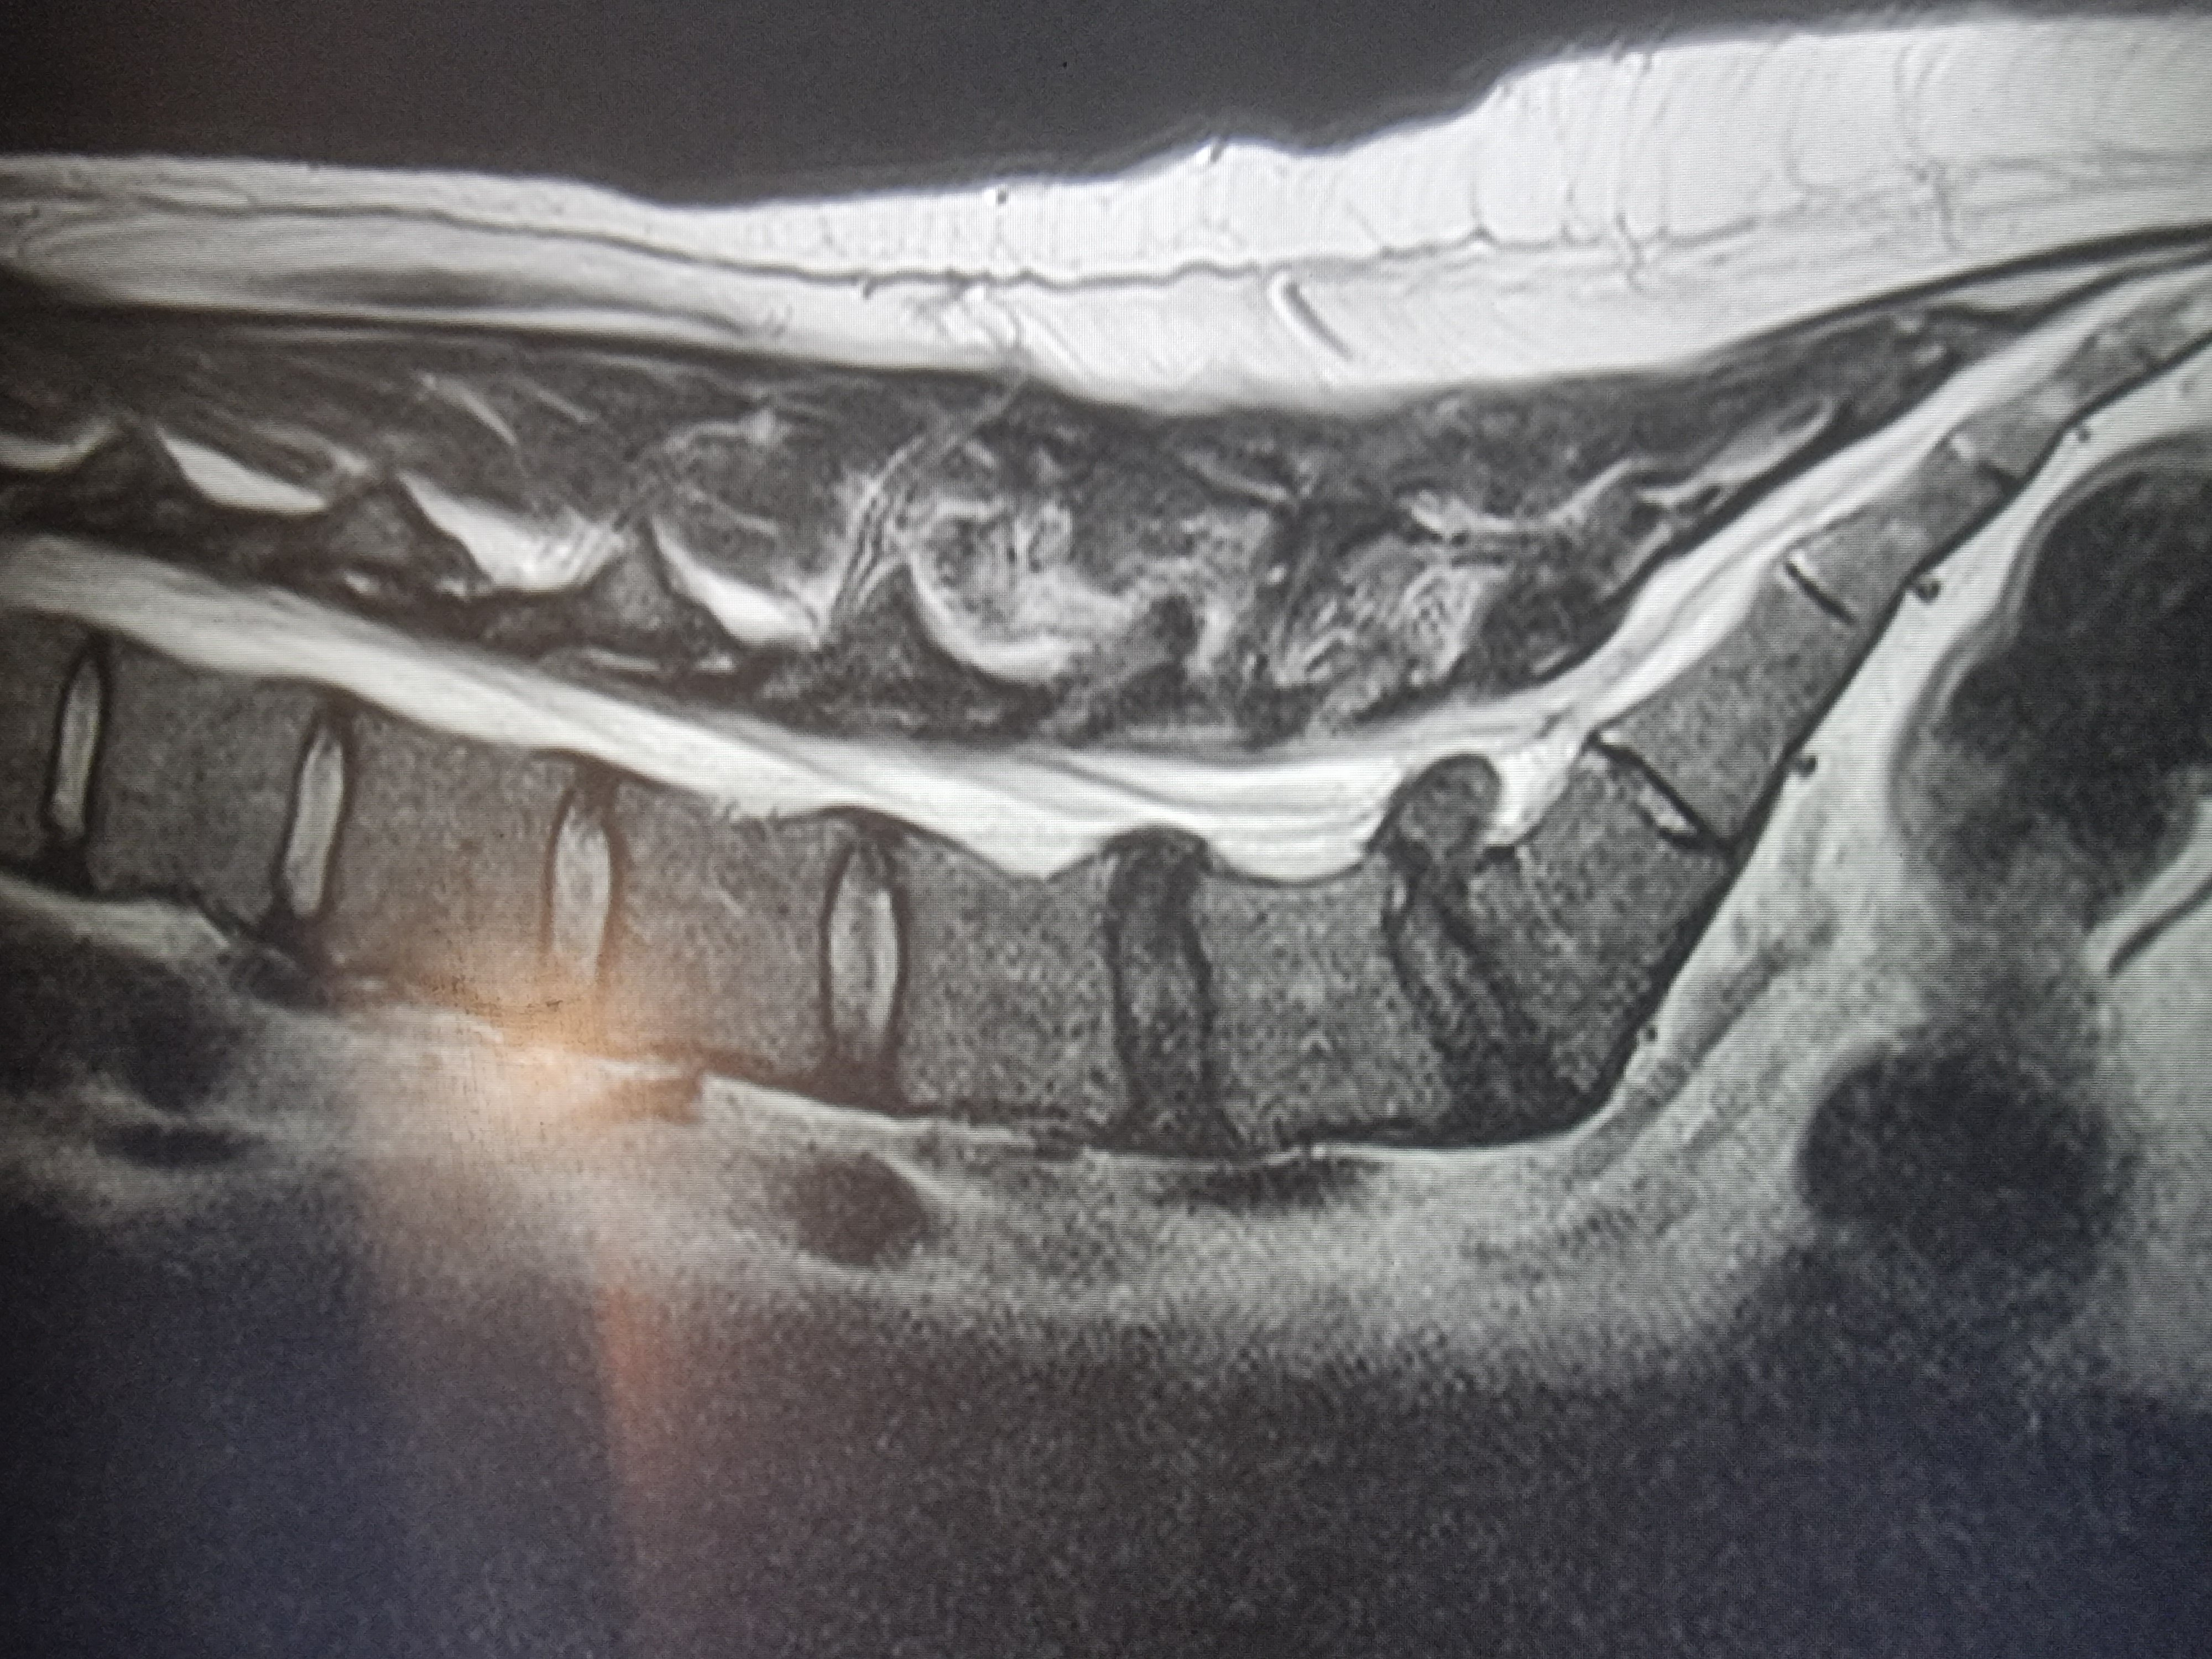

У меня болит зуб, его лечили, он продолжил болеть, его лечили еще раз, он продолжил болеть, его пролечили в третий раз, и угадайте что? Да, он продолжает болеть. Рентгены, кт, прицельные снимки в 4 разных клиниках - все это было сделано и врачи не видят проблемы. Чат джпт говорит это трещина, но ее тоже никто не видел и даже речи о ней не было. Я рылся на других сайтах и в тиктоке нашел тян, которая жаловалась на то же самое - зуб полечили, а он болит. Я списался с ней, спросил как дела, она сказала, что у нее нашли кариес еще на других зубах, пролечили и теперь они тоже болят. Она делала физио, ходила к неврологу, делала мрт, тоже ничего нет. Зубы пролечены и здоровы, но они болят. Что это за хуйня аноны?